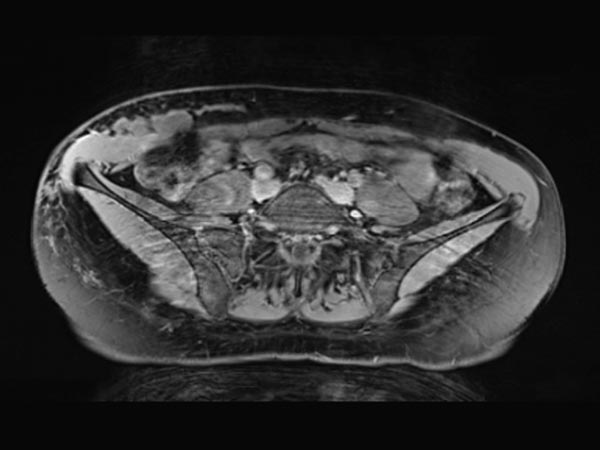

Transverse, T2-weighted, fat-suppressed MRI at the level of the iliac crest shows additional extension of the lymphatic malformation to the right flank. Only the epifascial portions of the abdominal wall and trunk wall are involved.